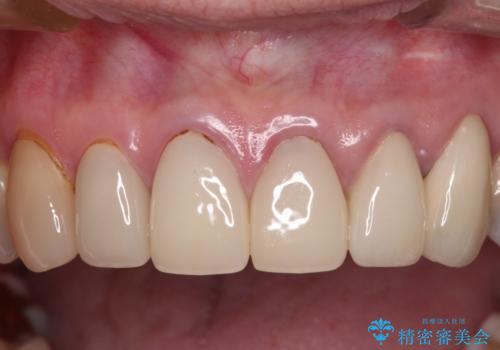

もげてしまった前歯をセラミッククラウンで自然に

- 前歯が土台ごと外れてしまったとのことで来院された患者様です。

土台は外れていましたが破折などの問題はなく、土台からの再治療で対応可能な状態でした。

隣の犬歯も神経が取り除かれていたしたが、ラミネートベニアで治療されており、裏側でむし歯が進行する可能性があったため、こちらも治療が必要と判断されました。

外れてしまったクラウンを保管しておき、新しいクラウン製作の際に技工所に送ることで、今までと同じような色合いに仕上げることができ、周囲のクラウンとバランスを取ることができます。